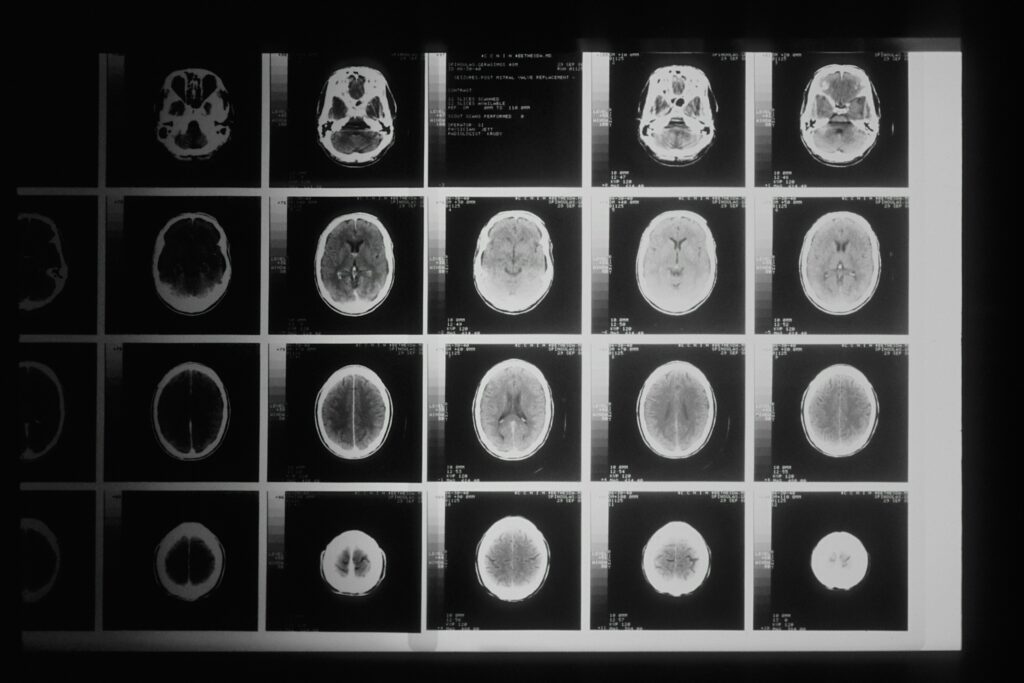

5. Trening mentalny fizycznie przekształca strukturę mózgu

Neuroplastyczność – zdolność mózgu do fizycznej reorganizacji w odpowiedzi na doświadczenie – należy do najważniejszych odkryć współczesnej neuronauki. ReSource Project dostarczył mocnych dowodów, że ukierunkowany trening mentalny stanowi formę doświadczenia zdolnego do rzeźbienia struktury mózgu.

Po zaledwie trzech miesiącach treningu naukowcy zaobserwowali mierzalne zmiany w grubości kory mózgowej. Co kluczowe, zmiany te były specyficzne dla trenowanych umiejętności:

- Trening społeczno-afektywny (moduł Uczuć) wiązał się ze zmianami strukturalnymi w obszarach odpowiedzialnych za empatię i współczucie.

- Trening społeczno-poznawczy (moduł Perspektywy) korelował ze zmianami w rejonach związanych z przyjmowaniem perspektywy innych i teorią umysłu.

Stopień pogrubienia kory w tych obszarach odpowiadał indywidualnym postępom uczestników w zadaniach mierzących daną umiejętność. Im większa zmiana strukturalna, tym wyraźniejsza poprawa behawioralna.

Szczególnie istotne było odkrycie dotyczące hipokampu – struktury mózgu kluczowej dla pamięci i regulacji reakcji na stres. Trening w module Uczuć prowadził do wzrostu objętości części CA1-3 hipokampu. Ten wzrost korelował bezpośrednio z obniżeniem poziomu kortyzolu w odpowiedzi na stres.

Innymi słowy, systematyczna praca nad różnymi aspektami inteligencji emocjonalnej – zarówno rozpoznawaniem i przetwarzaniem emocji, radzeniem sobie z trudnymi stanami emocjonalnymi towarzyszącymi stresowi (moduł Uczuć), jak i rozumieniem perspektyw innych ludzi oraz dystansowaniem się od własnych myśli (moduł Perspektywy) – nie tylko poprawia nasze relacje i samopoczucie. Fizycznie zmienia struktury mózgowe odpowiedzialne za zarządzanie stresem i funkcjonowanie społeczne. Nasze intencje i regularne praktyki mentalne mają mierzalną moc kształtowania organu, który je generuje.